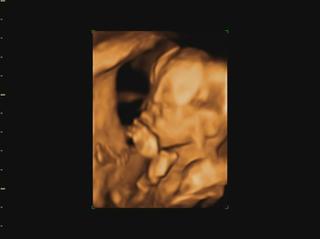

Ahojte kočky, konečne mam trošku času tak si idem spätne prečítať čo ste napísali... a pochváliť vám krásne brušinká 😀 medzi tým Vám pridám moje brušo a našu Izzy neposednú. Máme aj video, ale to som dala len FB, lebo tu sa pridať nedá. Fotky aj video je trochu rozmazané, lebo mala v kuse so sebou narabala... a ano pipik nam nedorastol... 😀